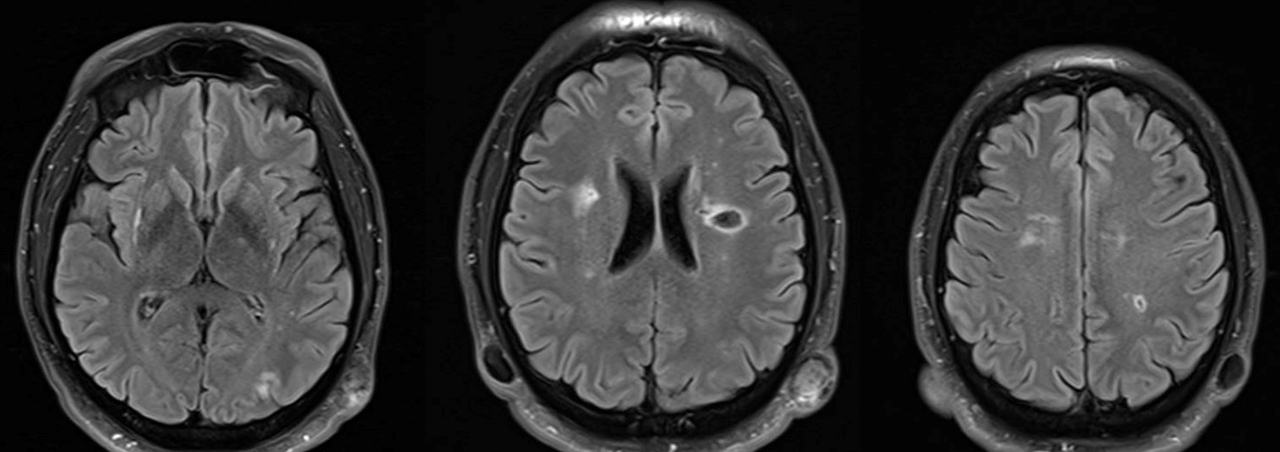

Le type d’hémianopsie est très important car il permet de localiser une atteinte neurologique, en connaissant le trajet des voies optiques.

Figure d’après le Collège des enseignants de neurologie (CEN). Altération aiguë de la vision.

Cette question supposait d’avoir bien en tête le schéma des voies optiques, et d’avoir des repères sur les principaux territoires vasculaires cérébraux et l’atteinte clinique associée. Il bien mentionné par le CEN que l’hémianopsie latérale homonyme gauche peut se voir dans un AVC sylvien superficiel droit.